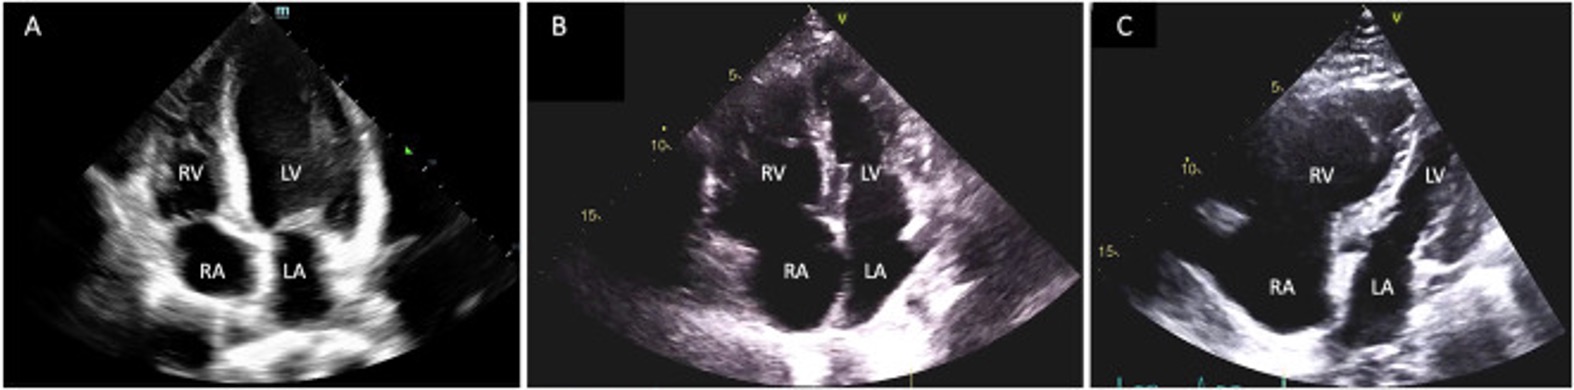

Imaging findings of severe right heart strain with bowing of the interventricular septum into the left ventricle, and severely elevated RV/LV ratio of 2.0. Backing of intravenous contrast into the liver veins as well. Emergent PERT consultation is recommended.

RV:LV ratio: Normal is .67:1, mild dilation is .67:1 to 1:1, moderate dilation is 1:1 to 1.5:1, and severe dilation is greater than 1.5:1

Septal Flattening (“D sign”)

McConnell Sign